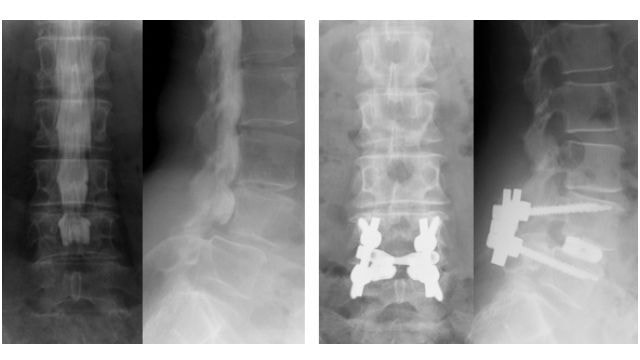

新しい脊椎固定術

脊椎固定術に関しては、Cortical Bone Trajectoryという、新しいインプラントの挿入方法を用いた手術を行っています。わきだ整形外科では、2011年12月より開始しました。九州で最初に、Cortical Bone Trajectoryを採用した椎体間固定術を成功させたは、楊 昌樹だと言われており、優秀な成績を収めています。Cortical Bone Trajectoryは、以前よりも切開が少なくて済み、筋肉の剥離や損傷が少なく、痛みや出血が少なくなる手術方法で、革新的な手術方法です。どの手術に対しても、真の低侵襲手術を目指して、最先端の治療を行っています。